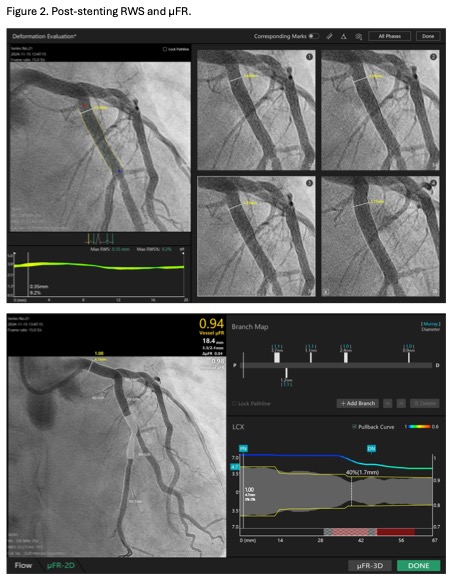

A 6Fr EBU 3.5 guiding catheter was engaged into the left main using right radial access. Distal LCX was wired using Rinato. Pre-dilatation was done using a 4.0/15 NC Scoreflex scoring balloon. Freesolve¢ç 4.0/18 was implanted at 10atm. Post-dilatation was done using 4.5/15 Pantera Neo balloon. Results including stent expansion were excellent based on angiogram (Video 3) and OCT (Video 4). The post procedure RWS and ¥ìFR were 9.2% and 0.94, respectively (Figure 2).Six months later, we performed a restudy coronary angiogram for this patient, showing patent mLCX (Video 5), completely degraded resorbable scaffold and resolution of the vulnerable plaque on OCT (Video 6). The RWS and ¥ìFR were 0.37mm (11%) and 0.97, respectively (Figure 3). The patient remained asymptomatic.

Case Summary